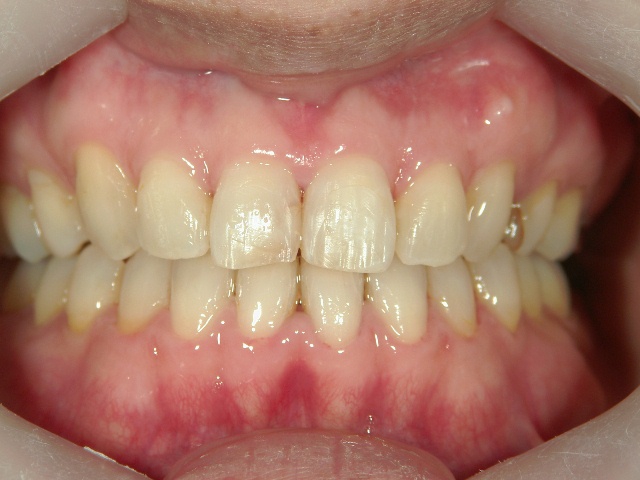

矯正歯科(全顎ワイヤー矯正)治療後

全顎ワイヤー矯正 症例(2)

36歳女性 磐田市

在住

治療期間2年6

ヶ月

矯正歯科 治療後